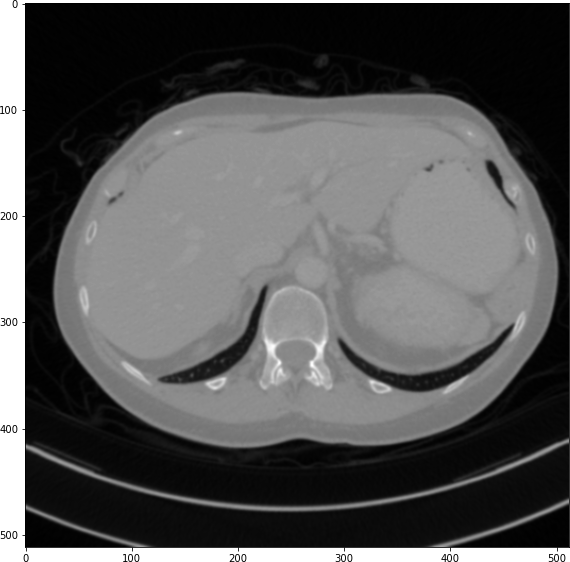

The results from all conducted experiments, represented as mean ±plus-or-minus\pm standard deviation, are tabulated in this section. We assessed the performance of our proposed simulation method against Simple Averaging, Gaussian Averaging, and Direct Downsampling. This was accomplished by simulating images with a thickness of 3mm from those with a thickness of 1mm, utilizing the 2016 Low Dose CT Grand Challenge dataset. The results outlined in Table III provide a comparative analysis of different thick-slice simulation methods used in two datasets from the 2016 Low Dose CT Grand Challenge. Both the PSNR and the RMSE were used as key performance indicators for these methods. The data clearly demonstrate that the proposed method significantly outperformed Simple Averaging, Gaussian Averaging, and Direct Downsampling in both datasets (D45 and B30). The highest PSNR values were obtained with the proposed method, yielding 49.7369 ±plus-or-minus\pm 2.5223 and 48.5801 ±plus-or-minus\pm 7.3271 for D45 and B30 datasets, respectively. The proposed method also registered the lowest RMSE with values of 0.0068 ±plus-or-minus\pm 0.0020 and 0.0108 ±plus-or-minus\pm 0.0099 for D45 and B30, respectively. These results indicate a superior level of accuracy and reliability in the proposed method. The statistically significant differences were confirmed by a Wilcoxon signed-rank test with p-value ¡ 0.05, implying that the improvements from the proposed method were not due to random chance. These findings support our first hypothesis that the proposed simulation method provides a more efficient and precise approach to thick-slice simulations compared to traditional methods. To provide a more comprehensive evaluation, visual comparisons from axial, coronal and sagittal plane were also undertaken, as depicted in Figures 2 to 4. In summary, Our proposed method demonstrated substantial enhancements in terms of both PSNR and RMSE, indicating a distribution more closely aligned with the authentic thick-slice image.

Refer to caption

(a) True Thick-slice image

(b) Simple Averaging

RMSE: 0.0329, PSNR: 35.6776

(c) Gaussian Averaging

RMSE: 0.0955, PSNR: 26.4221

(d) Direct Downsampling

RMSE: 0.0454, PSNR: 32.8776

(e) Proposed Simulation

RMSE: 0.0010, PSNR: 46.4076

Figure 2: Axial-plane thick-slice image quality comparison across four simulation methods.